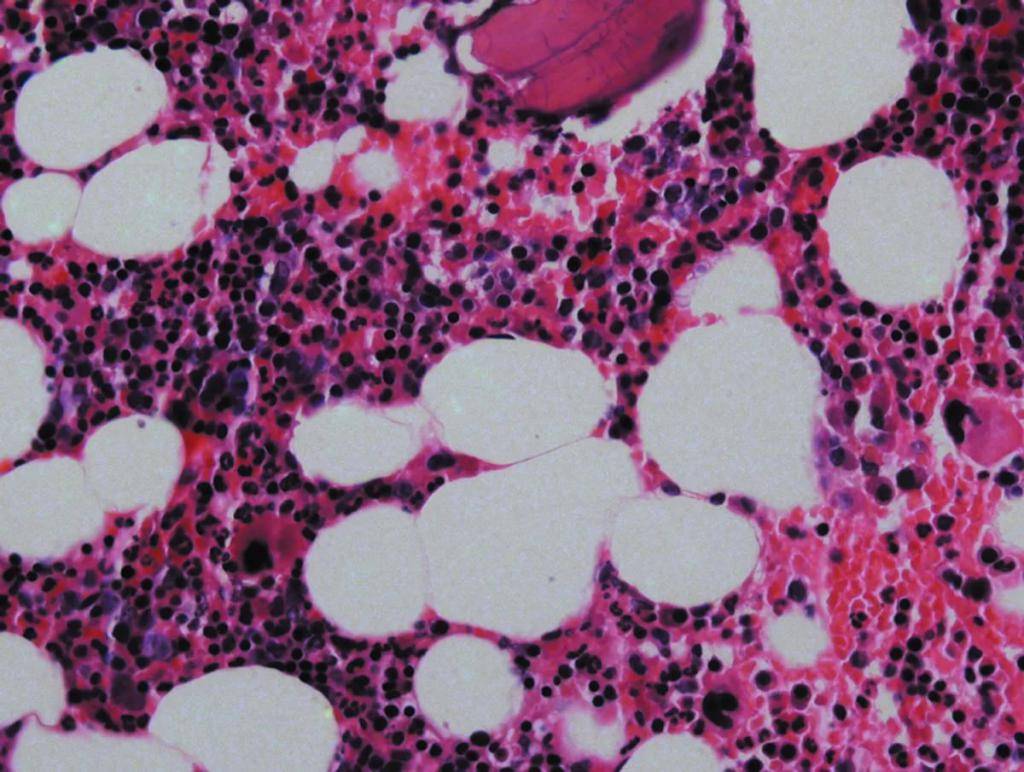

Гранулоциты имеют ядро, разделенное на несколько сегментов. При этом оно неправильной формы. Клетки образуются в костном мозге и составляют до 70% всех лейкоцитов. Жизненный цикл гранулоцитов составляет от 3 до 10 суток. По истечении нескольких дней они погибают. Их заменяют новые клетки.

Гранулоциты — это собирательный термин. К данным клеткам относятся эозинофилы, базофилы и нейтрофилы.

GRA – это условное обозначение одной из разновидностей неоднородных групп полиморфноядерных клеток, для которой характерно большое сегментированное ядро и наличие в цитоплазме гранулем, светящихся в микроскопе. Количество зернистых лейкоцитов в плазме крови является стабильной величиной.